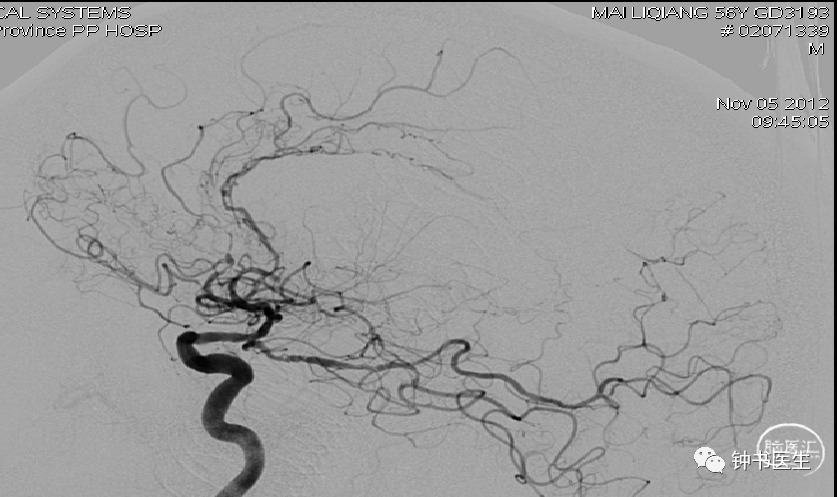

病例1

56y,意识不清伴右侧肢体无力5小时,GCS8分

再灌注损伤(出血):需降压

出血疼痛、烦躁,血压高

镇静镇痛影响神志观察

2012-11-8 CT

左颞部脑梗加重,出血渗出点增多。继续加强镇静镇痛治疗。

2012-11-10 CT

病情趋稳定,转出监护室治疗。